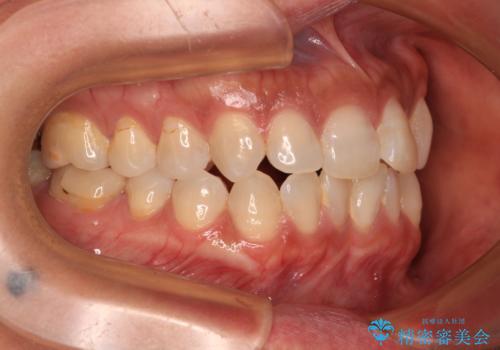

- 前歯のクロスバイトを気にして来院された患者様です。

上下ともに、前歯部を中心にやや叢生が認められる程度であったため、ワイヤーでもインビザラインでも、どちらでも対応可能な状態でした。